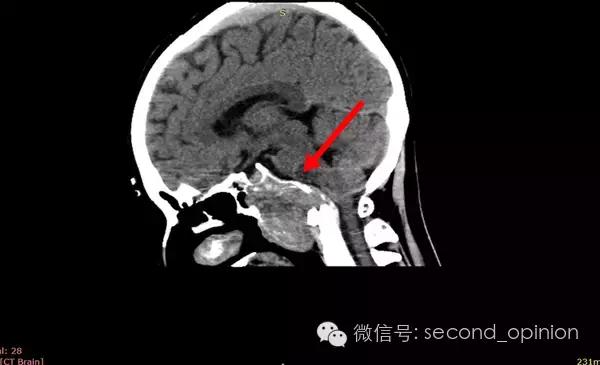

患者自2013年6月起无诱因出现吞咽困难,伴吐字不清症状,自觉舌肌无力一个星期,偶有头痛发作,不伴呛咳,呕吐,无抽搐发作。当时耳鼻喉科做相关检查,咽部无异常表现。行头部CT检查发现颅内占位,范围约43*30mm。保守治疗,后病情稳定,未发现症状明显加重。

至2014年1月,出现左耳耳鸣,表现为低调杂音,未发现听力明显下降,偶有脸部麻木,无面瘫。行MRI检查,颅内占位范围约60*45*47mm。2014年2月2日第一次手术,行内镜导航下经蝶窦颅底肿瘤切除术,切除体积约50*45*50mm,手术顺利,术后头痛症状消失。左耳低调耳鸣术后消失两周后再次出现,右耳术后出现偶发轻度耳鸣。2014年5月4日第二次手术,行内镜口鼻蝶入路脊索瘤切除术,切除肿瘤体积45*40*50mm,过程顺利,术后耳鸣消失,病情稳定后出院。

2014年6月15日 进行射波刀放疗,32.5Gy/5fx,剂量曲线69%包绕,治疗期间对症脱水,减轻放疗反应,完成全部治疗后出院。

2014年12月 进行质子放射治疗。

病理结果:脊索瘤

免疫组化:CK+、vimentin+、S-100-、CK8/18+、Ki-67约10%、EMA+

质子治疗:

日本国立癌症中心 2014年12月3日-12月31日

总剂量40GyE

2014年9月1日MRI(手术治疗前)

质子治疗前